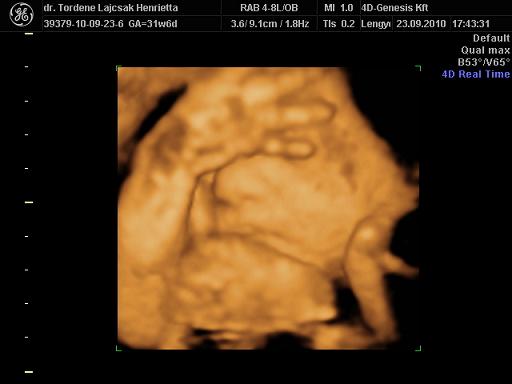

tegnap voltunk Uh-n. minden rendben van vele, egyre nagyobb. :)

méreteink:

BPD: 79,7 mm

HC: 292,5 mm

AC: 268,5 mm

FL: 57,8 mm (ezt nem tudta pontosan lemérni, mert érdekesen pózolt )

súly: 1700 g. (netes kalkulátor alapján 1750)

rakok róla néhány képet. :oops: és már 32 hetesek vagyunk...lassan finish.. :)